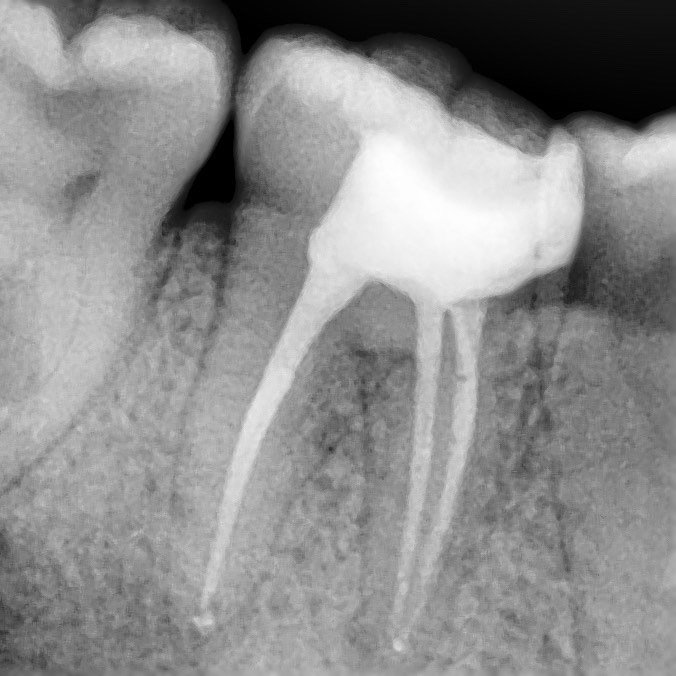

Successful endodontic treatment requires careful preparation, disinfection and sealing of the canals.

• Easily locate the entrance to the canal with maximum preservation of the tooth structure.

• Identify additional canals and anatomical features.

• Control the removal of pulp and organic tissue from the canal, which protects us from secondary infection.

• Remove elements that impede access to channels.

• In the case of repeated endodontics, it plays an irreplaceable role.

The most common complication encountered by the dentist during endodontic treatment is perforation and instrument breakage in the canal, resulting in the majority of patients losing a tooth. We can easily deal with such difficulties through a microscope.

Multiple increase

careful treatment of canals